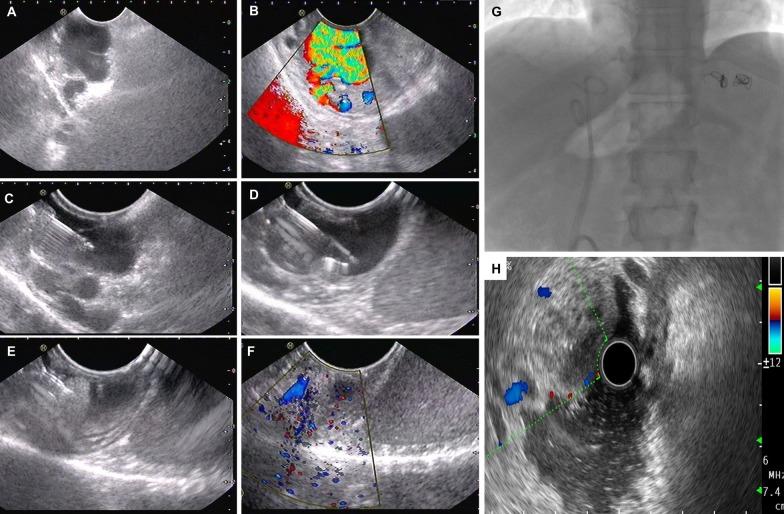

Gastric varices are encountered less frequently than esophageal varices. Nonetheless, gastric variceal bleeding is more severe and associated with worse outcomes. Conventionally, gastric varices have been described based on the location and extent and endoscopic treatments offered based on these descriptions. With improved understanding of portal hypertension and the dynamic physiology of collateral circulation, gastric variceal classification has been refined to include inflow and outflow based hemodynamic pathways. These have led to an improvement in the management of gastric variceal disease through newer modalities of treatment such as endoscopic ultrasound-guided glue-coiling combination therapy and the emergence of highly effective endovascular treatments such as shunt and variceal complex embolization with or without transjugular intrahepatic portosystemic shunt (TIPS) placement in patients who are deemed 'difficult' to manage the traditional way. Furthermore, the decisions regarding TIPS and additional endovascular procedures in patients with gastric variceal bleeding have changed after the emergence of 'portal hypertension theories' of proximity, throughput, and recruitment. The hemodynamic classification, grounded on novel theories and its cognizance, can help in identifying patients at baseline, in whom conventional treatment could fail. In this exhaustive review, we discuss the conventional and hemodynamic diagnosis of gastric varices concerning new classifications; explore and illustrate new 'portal hypertension theories' of gastric variceal disease and corresponding management and shed light on current evidence-based treatments through a 'new' algorithmic approach, established on hemodynamic physiology of gastric varices.

胃静脉曲张比食管静脉曲张少见。然而,胃静脉曲张出血更严重,预后更差。传统上,根据位置和范围描述胃静脉曲张,并根据这些描述提供内镜治疗。随着对门脉高压和侧支循环动态生理学认识的提高,胃静脉曲张的分类已得到改进,包括基于血流动力学途径的流入和流出。这些新的治疗方式如内镜超声引导下胶圈联合治疗以及分流和静脉曲张复合栓塞等高度有效的血管内治疗的出现,改善了胃静脉曲张疾病的管理,即使对于传统治疗方式认为“困难”的患者也是如此。此外,在出现“门脉高压接近、吞吐量和招募理论”后,关于胃静脉曲张出血患者的 TIPS 和其他血管内手术的决策发生了变化。基于新理论及其认知的血流动力学分类有助于在基线时识别可能常规治疗失败的患者。在这篇全面的综述中,我们讨论了传统和血流动力学诊断胃静脉曲张的新分类;探讨和阐明了胃静脉曲张疾病的新“门脉高压理论”及其相应的管理,并通过基于胃静脉曲张血流动力学生理学的“新”算法方法阐明了当前基于证据的治疗方法。